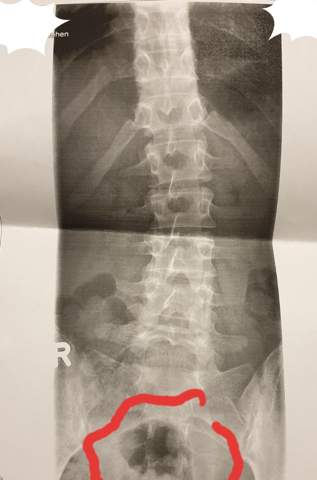

War vorher bzw heute morgen beim Orthopäden und habe mich wegen meiner Muskelentzündung röntgen lassen. Der große schwarze Fleck im Bereich des Magens ist am ehesten die Luft im Magen. Mein Orthopäde konnte sich auch nicht wirklich erklären was das ist.

Diese steigt nach oben und ist dann unterhalb der linken Zwerchfellkuppel als sehr röntgendurchlässig zu sehen. Leukoplasien handelt erkennt man Veränderungen im Knochen oftmals erst auf einem Röntgenbild. Ist das ein Bluterguss.

Wegen ihrer Dichte fangen Knochen fast die ganze Röntgenstrahlung auf sie sind daher deutlich als weiße oder graue Konturen auf dem Röntgenbild zu erkennen. Hyperdensität oder einen schwarzen Fleck eine Osteolyse sehen.

Wir hoffen wir konnten Ihnen weiterhelfen - Ihr Lifeline Gesundheitsteam. Hilfe Röntgenbild schwarzer punkt knochen Ich denke als Laie kann man keine Röngenbilder beurteilenDieser Fleck ist möglicherweise ganz anders zu interpretieren als Sie das jetzt tunIch würde mir dazu keine Gedanken machenzumal Ihre Beschwerden ja auch an ganz anderer Stelle gelagert sindOb das ein Bildfehler ist wage ich zu bezweifelndas wird sich wohl so gehörenAber. Die Diagnose erfolgt durch eine Kernspintomographie MRT. Röntgenbilder und Ultraschall können ein Knochenmarködem BME bone marrow edema nicht darstellen. Röntgenbilder und Ultraschall können ein Knochenmarködem BME bone marrow edema nicht darstellen. Wir hoffen wir konnten Ihnen weiterhelfen - Ihr Lifeline Gesundheitsteam. Die Geräte werden meist zur Beurteilung von Herz und Lunge Knochen und Gelenken eingesetzt. Diese steigt nach oben und ist dann unterhalb der linken Zwerchfellkuppel als sehr röntgendurchlässig zu sehen. Ein Röntgenbild für einen Laien nicht sehr einfach zu interpretieren.

Ein Röntgenbild für einen Laien nicht sehr einfach zu interpretieren. Mein Orthopäde konnte sich auch nicht wirklich erklären was das ist. Diese steigt nach oben und ist dann unterhalb der linken Zwerchfellkuppel als sehr röntgendurchlässig zu sehen. Dort lassen sich entsprechende Signalveränderungen feststellen - im abgebildeten MRT zeigen sich im schwarzen Knochen weiße Flecken als Zeichen einer Flüssigkeitseinlagerung. Eine dunkle Stelle auf der Aufnahme sagt zunächst nur aus dass der Knochen hier die Röntgenstrahlen leichter hindurch lässt also das Gewebe nicht so dicht ist. Die Diagnose erfolgt durch eine Kernspintomographie MRT. Auf dem Röntgenbild sind weiße Flecken oben rechts im rundlichen Knochen denke Mal dass das das Ende des Oberarms ist zu sehen.